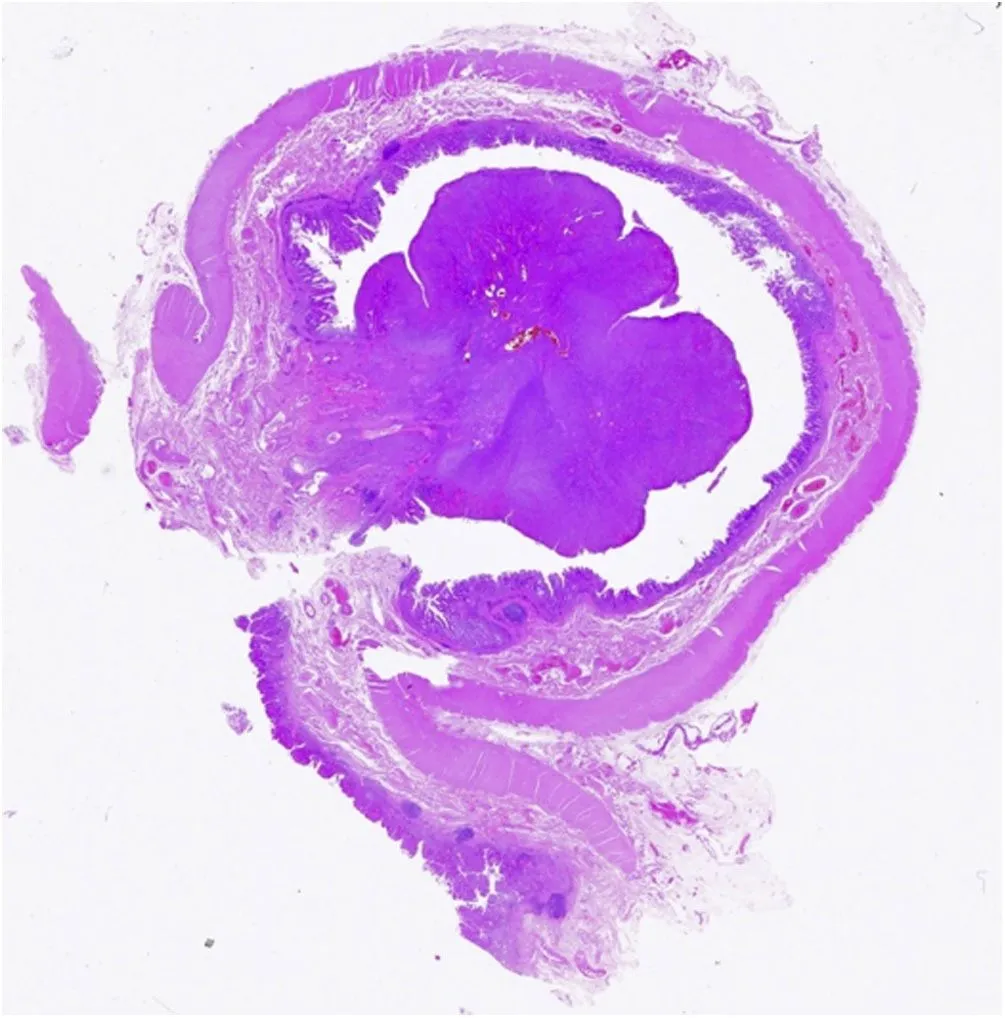

При патоморфологическом исследовании обнаружено язвенное полипоидное поражение 2 × 2,8 см в диаметре в окружении слизистой оболочки с бархатистостью (рис. 2).

Рисунок 2 [1].